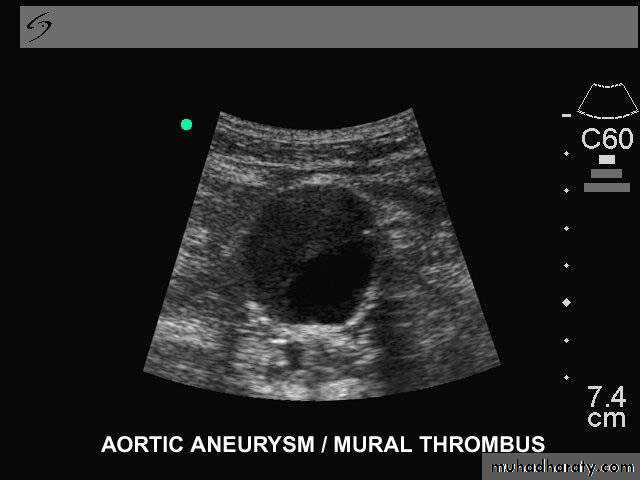

• Ultrasonography• Duplex ultrasound

Ultrasound & Duplex Ultrasound: